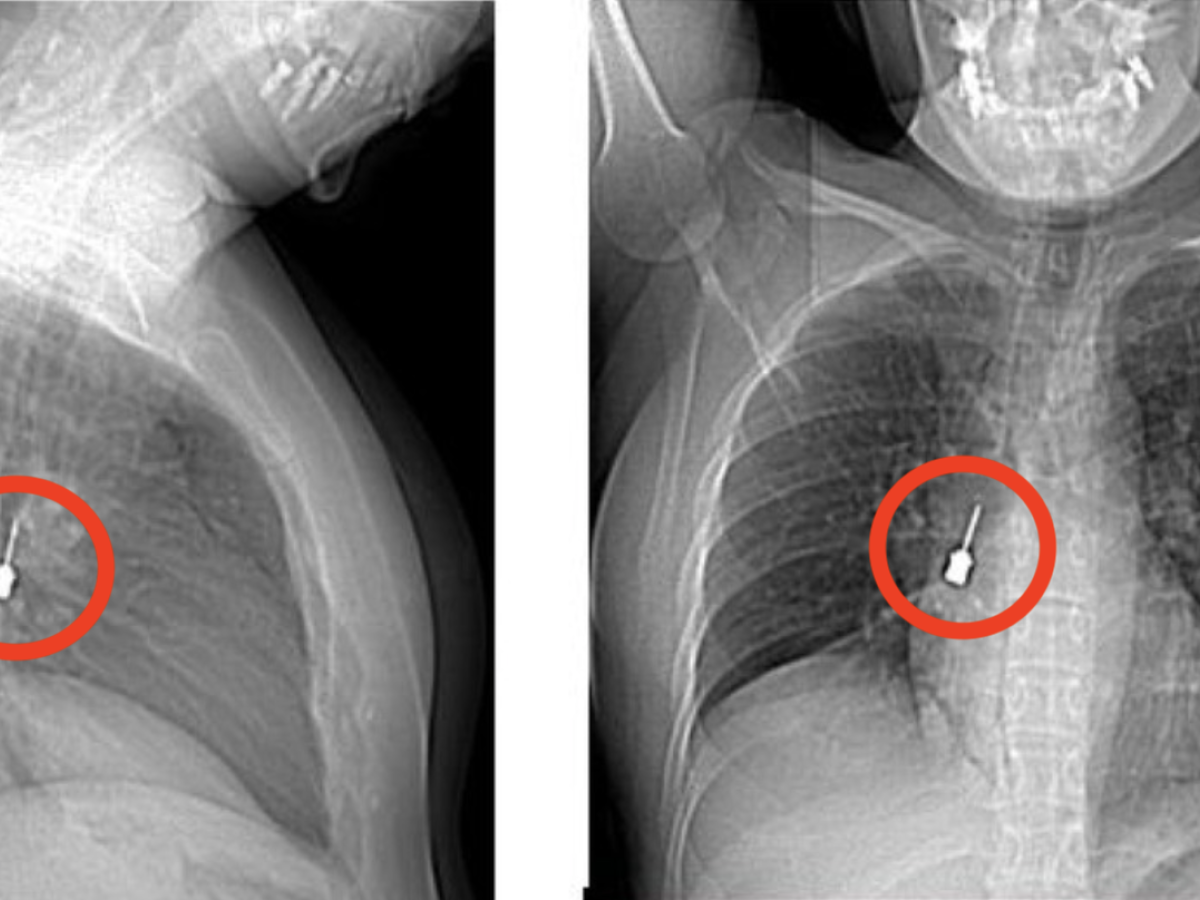

Una giovane donna si è presentata al Pronto Soccorso del Grande Ospedale Metropolitano (G.O.M.) di Reggio Calabria dopo giorni di tosse persistente e dolore intenso al petto. I medici, dopo aver visionato una Tomografia Computerizzata (un esame diagnostico di imaging medico che permette di ottenere immagini dettagliate dell’interno del corpo utilizzando raggi X e un computer), hanno fatto una scoperta sorprendente, un cacciavite odontoiatrico accidentalmente inalato era rimasto incastrato nel bronco lobare inferiore del polmone destro, provocando anche un pneumomediastino, ossia la presenza di aria nello spazio tra i due polmoni. 🔗 Leggi su Ilgiornale.it

Tosse e dolore al petto, i medici scoprono un cacciavite odontoiatrico incastrato nel bronco di una donna - Un cacciavite odontoiatrico inalato accidentalmente e rimasto incastrato in un bronco polmonare. msn.com